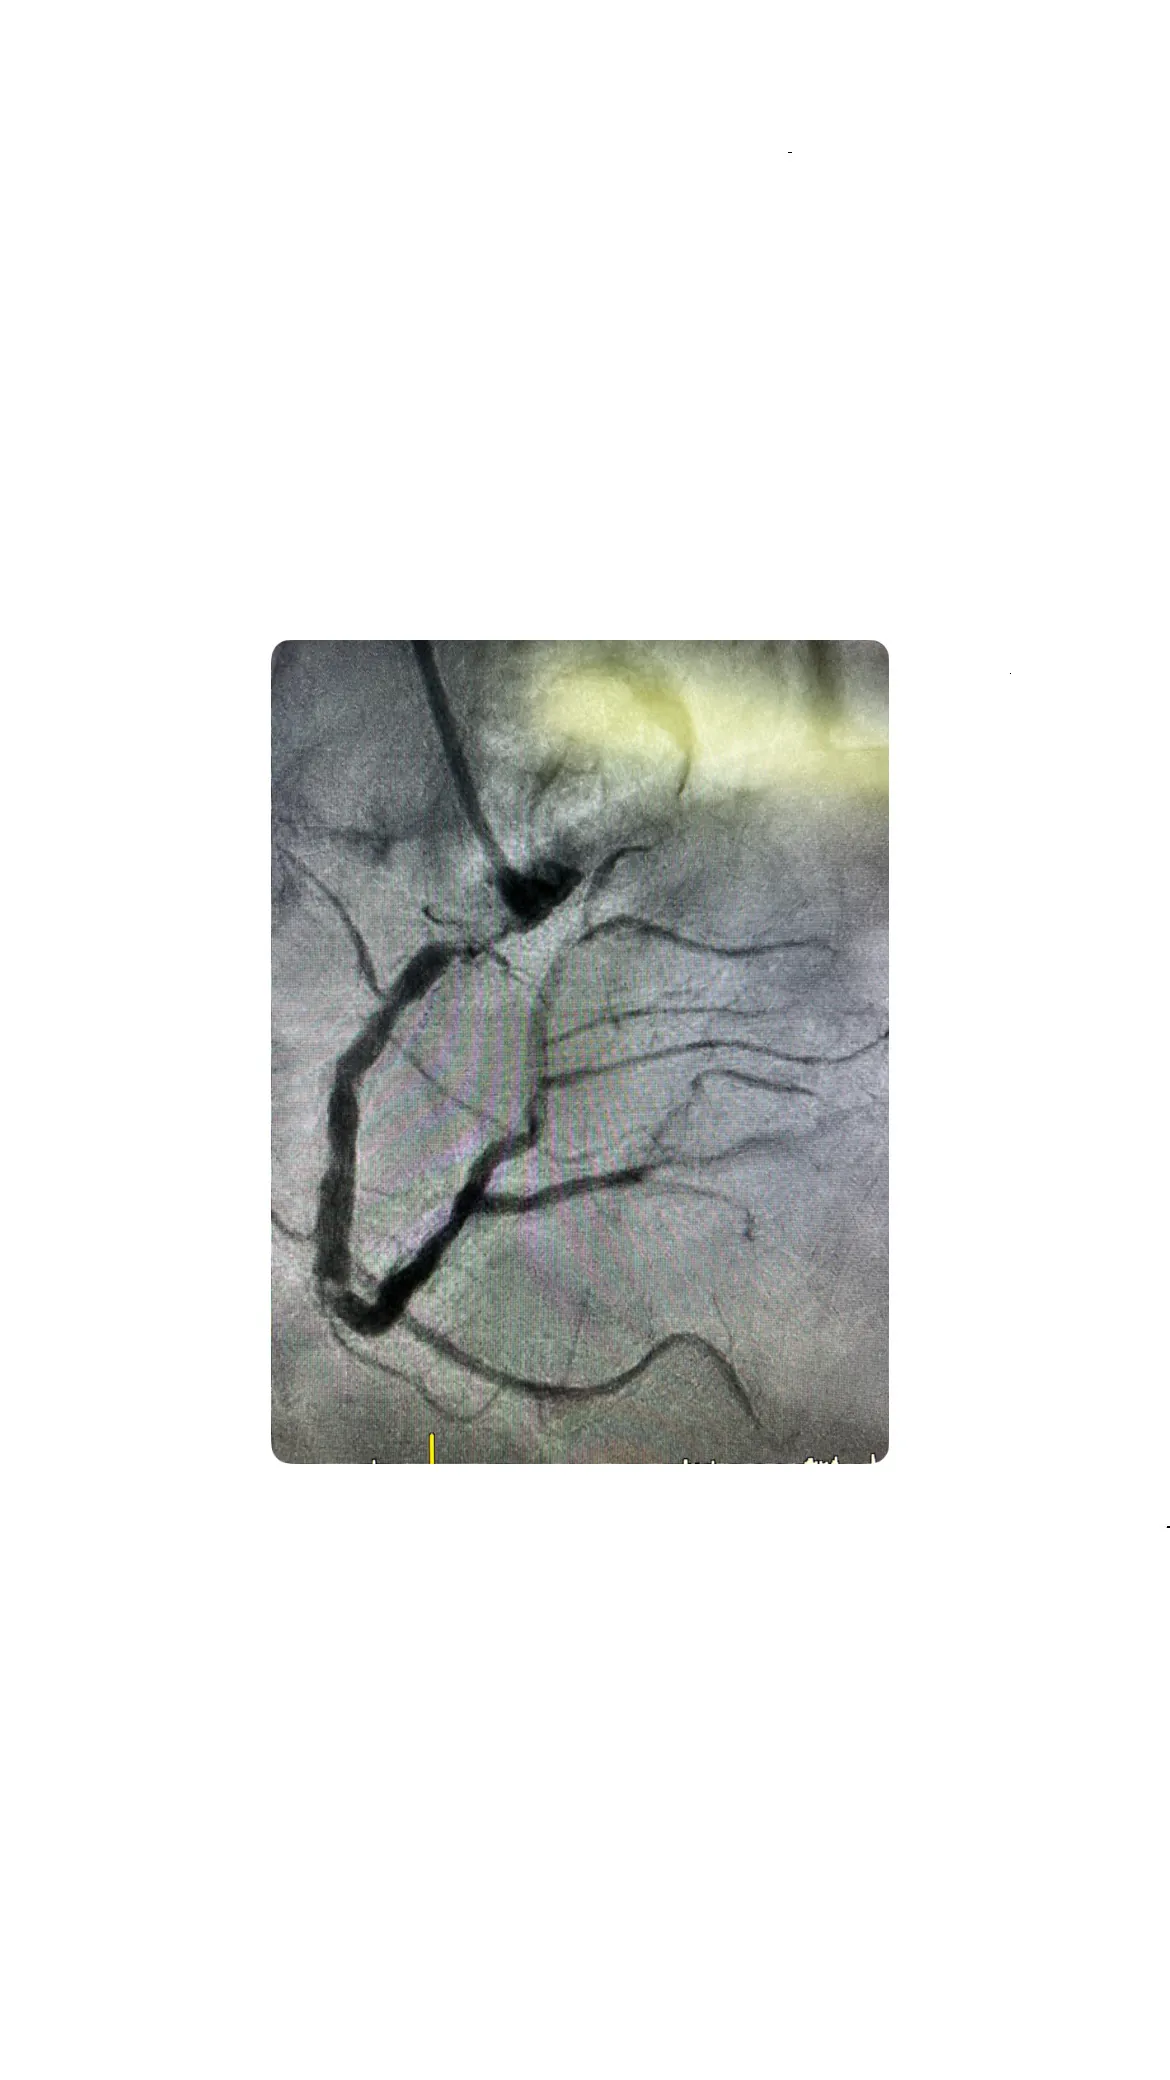

Hallazgos angiográficos: lesión de las 3 arterias

Los hallazgos angiográficos revelaron una lesión crítica en las tres arterias coronarias principales. La arteria coronaria derecha estaba casi ocluida a nivel osteal, mientras que la descendente anterior mostraba un deterioro significativo. Estos resultados confirman la gravedad de la enfermedad coronaria en el paciente y la necesidad de una intervención cuidadosa.